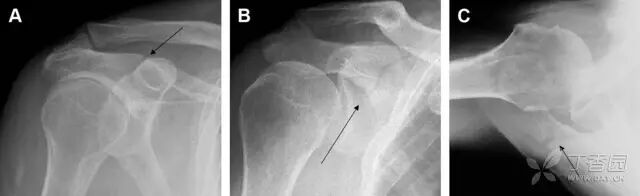

在常规前后位片上,大结节与肱骨头重叠,骨折不易发现,外旋位前后位片有助于诊断。

图 1 大结节骨折。(A)脂肪抑制序列斜冠状位 MRI,显示肱骨大结节线性骨折无移位(箭头)与周围骨水肿;(B)外旋位前后位(AP)片,证实大结节骨折(箭头),典型的骨折愈合过程中的骨吸收表现;(C、D)初诊时内旋位、外旋位前后位片,初诊时漏诊,仔细回顾影像,内旋伞下可见双密度影(椭圆),骨皮质中断(箭头)

多发生于摔倒时,手掌撑地,受到轴向、外翻应力所致。常规的前后位片容易漏诊,常需加拍内斜位、外斜位、桡骨头-肱骨小头位片。后脂肪垫可见(位于鹰嘴窝内,一般不可见)和/或前脂肪垫抬高常提示骨性损伤。

图 2 桡骨头骨折。前后位(A)和侧位(B)片示后脂肪垫抬高(黑色箭头),前脂肪垫抬高(白色箭头),呈「帆船征」,其它表现正常;外斜位(C)和桡骨头–肱骨小头位(D)示桡骨头关节内骨折线(虚线黑箭头)累及桡骨颈(虚线白箭头)

肩胛骨几何形状复杂,受到邻近其它骨性结重叠阻挡,且肩胛骨骨折少见,因此容易漏诊。当存在解剖变异时,诊断更为困难。

图 3 肩胛骨骨折正侧位片:由于骨块的叠加,(A)前后位片示「V」形高密度影(*),肩胛颈下方可见骨皮质碎片(箭头);(B)侧位片示骨皮质中断,骨折段移位,但由于肱骨的重叠遮挡,决断往往比较困难

喙突骨折可发生于直接暴力、肩关节脱位过程的肱骨头撞击、以及撕脱骨折(肱二头肌短头、喙肱肌)。

其中喙突基底部骨折最多见,常发生于直接暴力或肱骨头前脱位,骨折可延伸至关节盂。

而撕脱骨折多为喙突尖部的骨折。需要加拍腋位和 Stryker 位片(X 射线束以喙突为中心并头倾 10°,手臂外展,这样可以避开骨性结构的阻挡)。

有时,负重位片可发现并存的肩锁关节脱位,将有助于诊断。

图 4 喙突骨折。66 岁男性患者,射击后右肩前方疼痛。(A)内旋位前后位片投影隐约可见喙突基底部骨折(白色箭头),(B)外旋位前后位片投影结构存在重叠,(C)腋位投影时可良好显示。(D~F)喙突骨折伴 Hill-Sachs 损伤:肩关节脱位后慢性疼痛,喙突骨折块(*)向前外侧移位(双箭头),在外旋前后位(D)及腋位(E)片上均可显示,在内旋位前后位(F)片上,喙突被遮挡,但可见肱骨头 Hill-Sachs 损伤。(G、H)喙突骨折伴肩锁关节脱位,肩锁关节分离(白色双箭头),而喙锁间距正常(黑色的双箭头),应警惕喙突骨折。(I)喙突与肩峰骨化中心:对于未成年人,喙突与肩峰骨化中心可同时存在,易与骨折混淆,此时,拍对侧的 X 线片对比将有助于诊断。

肩峰骨折为高能量损伤,多由直接暴力导致,好发于中青年患者,多伴有肩关节其它结构损伤。有必要拍摄 Rockwood 位(前后位片,X 线束尾倾),特别有利于显示肩峰下部及肩峰下间隙。

图 5 肩峰骨折。内旋位前后位(A)片上,骨折线几乎被喙突完全遮挡, 但是在标准前后位(B)和腋位(C)片上可见骨折线